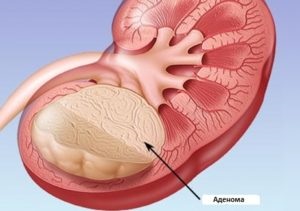

Există o patologie numită adenom de rinichi. Aceasta este o tumora benigna, care se află în stadii incipiente de dezvoltare nu are loc, și într-o stare de neglijare poate fi renăscut în oncologie.

Rinichi adenom - o tumoare benigna, aceasta se dezvoltă lent, consistența gros, cu limite clare. Educația este dimensiunea de doi milimetri la treizeci de milimetri.

În cazul în care patologia depășesc aceste limite, atunci putem vorbi despre maligna a tumorii. În plus, nu este întotdeauna posibil să se facă distincția de educație oncologie maligne, folosind un studiu diferențial.

Nu putem spune că adenomul este tratată într-un mod special. Uneori este faptul că pacientul imediat după diagnosticarea bolii, se spune că acesta trebuie să fie eliminate urgent. Astfel, putem salva restul de rinichi.

Dar când anomalia este mai mică de treizeci de milimetri, aceasta nu poate fi atins, mai ales în cazul în care crește foarte încet și nu progresează.

Atunci când intervenția chirurgicală, medicul va lua în considerare rezultatele examinării histologice după biopsie. În cazul în care se confirmă oncologie, atunci se va decide cu privire la îndepărtarea completă a organului.

Dacă nu există nici oncologie, si adenom a lovit doar o parte din ea, apoi scoateți zona afectată. După ce nu este utilizat chimioterapeutici si tratamente de radiatii.